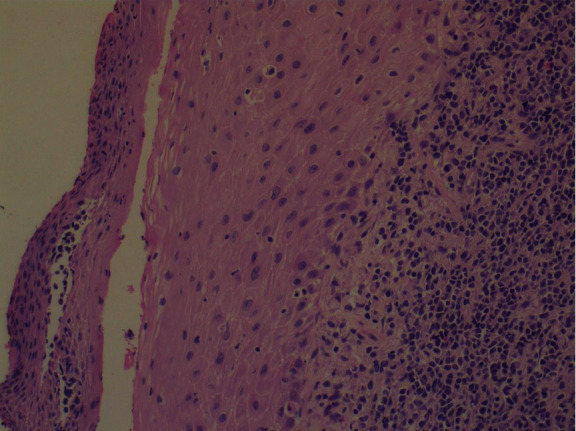

The patient had further consultation to discuss the details of the management plan. Punch biopsies for histological confirmation and further evaluation were decided. The histological result confirmed both the clinical impression and the cytological result leading to the diagnosis of “infiltration of the cervix by leukemic blasts” (Figures 8 and 9).

Figure 8.

Histology.

Figure 9.